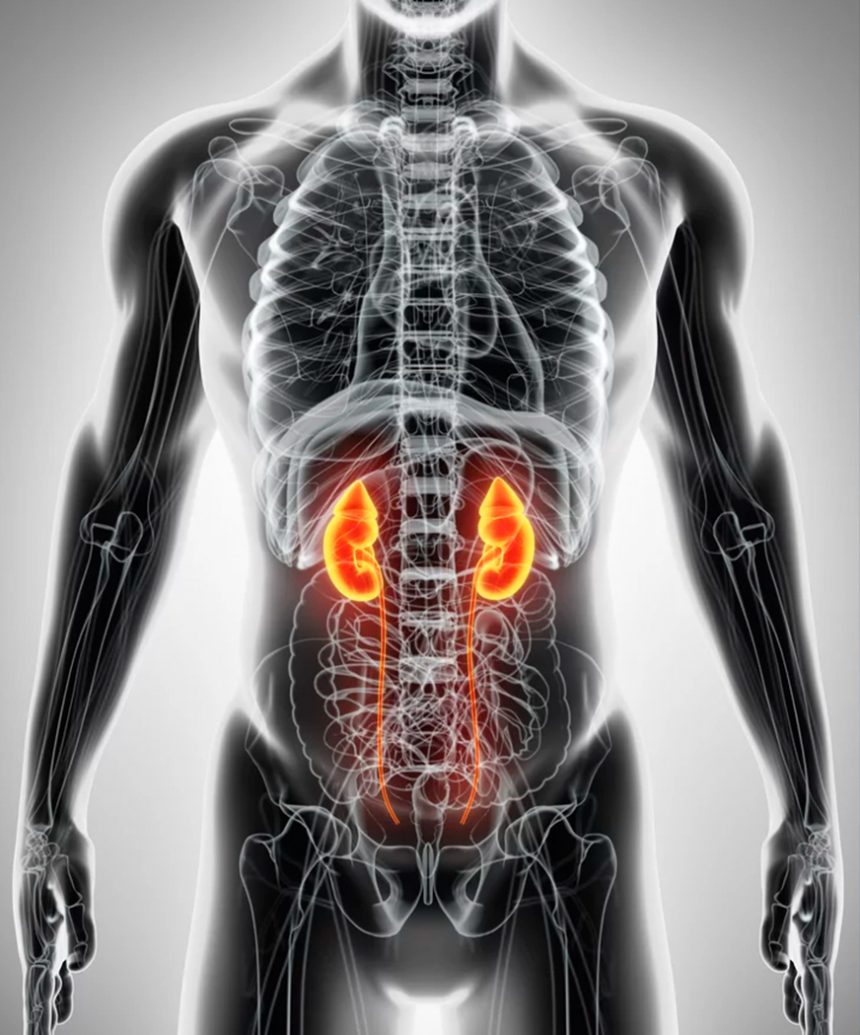

Urología